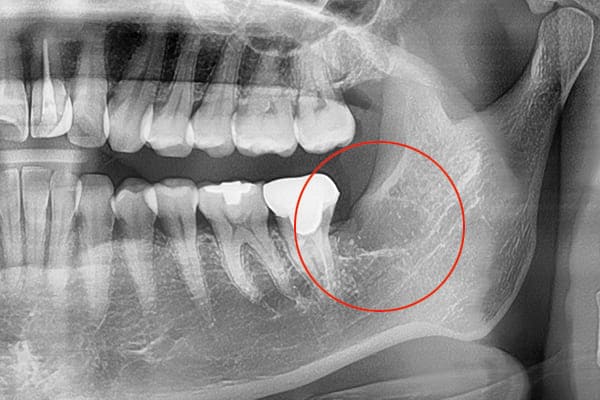

埋もれている水平埋伏の親知らず

歯ぐきの中で完全に真横に生えてしまうタイプです。

この親知らずを水平埋伏智歯と言います。

このタイプは、ほとんどが下顎のケースです。真横に生えているので、抜歯の際は難易度が高く2~3つに砕いて分けて抜歯をします。